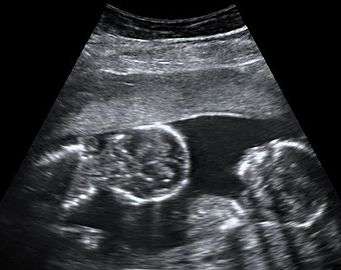

By performing an obstetric ultrasound at a gestational age of 10–14 weeks, monochorionic-diamniotic twins are discerned from dichorionic twins. The presence of a "T-sign" at the inter-twin membrane-placental junction is indicative of monochorionic-diamniotic twins (that is, the junction between the inter-twin membrane and the external rim forms a right angle), whereas dichorionic twins present with a "lambda (λ) sign" (that is, the chorion forms a wedge-shaped protrusion into the inter-twin space, creating a rather curved junction).[4] The "lambda sign" is also called the "twin peak sign". At ultrasound at a gestational age of 16–20 weeks, the "lambda sign" is indicative of dichorionicity but its absence does not exclude it.[5]

In contrast, the placentas may be overlapping for dichorionic twins, making it hard to distinguish them, making it difficult to discern mono- or dichorionic twins on solely the appearance of the placentas on ultrasound.